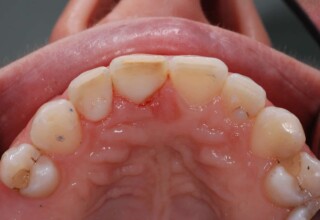

Αποκατάσταση διαστημάτων μεταξύ κεντρικών και πλαγίων τομέων

Τα διαστήματα έχουν δημιουργηθεί κυρίως λόγω των στενών πλαγίων. Μετά την ολοκλήρωση της ορθοδοντικής θεραπείας τα διαστήματα “έκλεισαν” με την τοποθέτηση δύο αποκαταστάσεων σύνθετης ρητίνης.